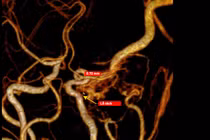

Các kết quả thăm dò cận lâm sàng sau đó cho thấy động mạch cảnh trong bên phải của người bệnh bị hẹp rất khít (>90%) ngay từ lỗ vào, kèm theo nhiều mảng xơ vữa. Ngoài ra, hệ mạch vành cũng ghi nhận hẹp trên 90% tại động mạch liên thất trước.

dong-mach.jpg